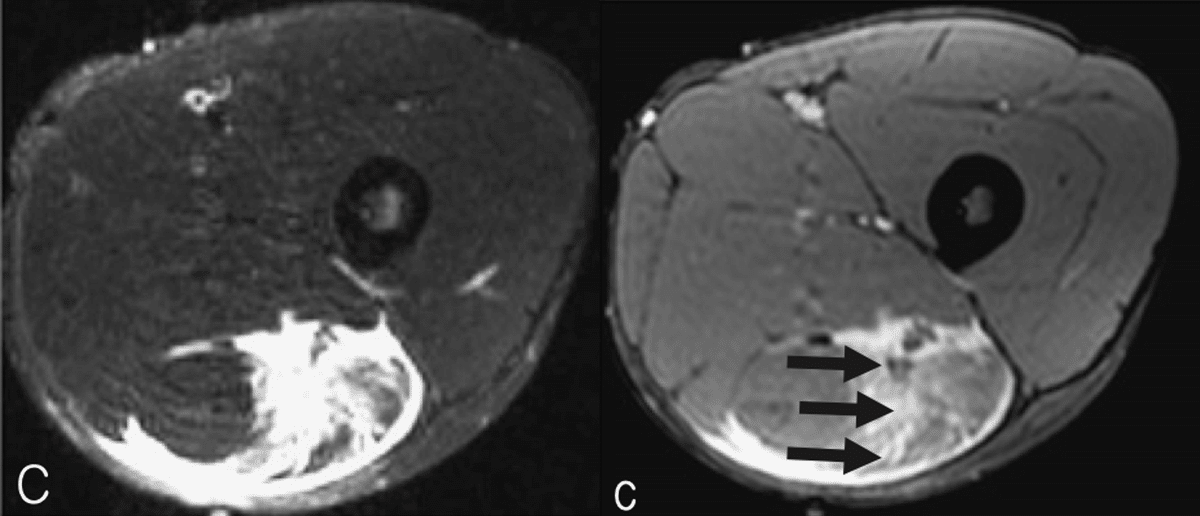

・Ⅱ型3度

(Pedret C, J Belg Soc Radiol. 2022から引用)

全周性に腱膜の連続性が確認できない

(奥脇 透:大腿二頭筋肉ばなれの MRI 分類、臨床スポーツ、2019より引用)